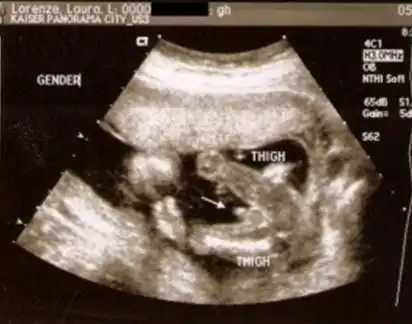

转帖哦,,精心收集男宝女宝b超图片数张!附b超特徵总结!